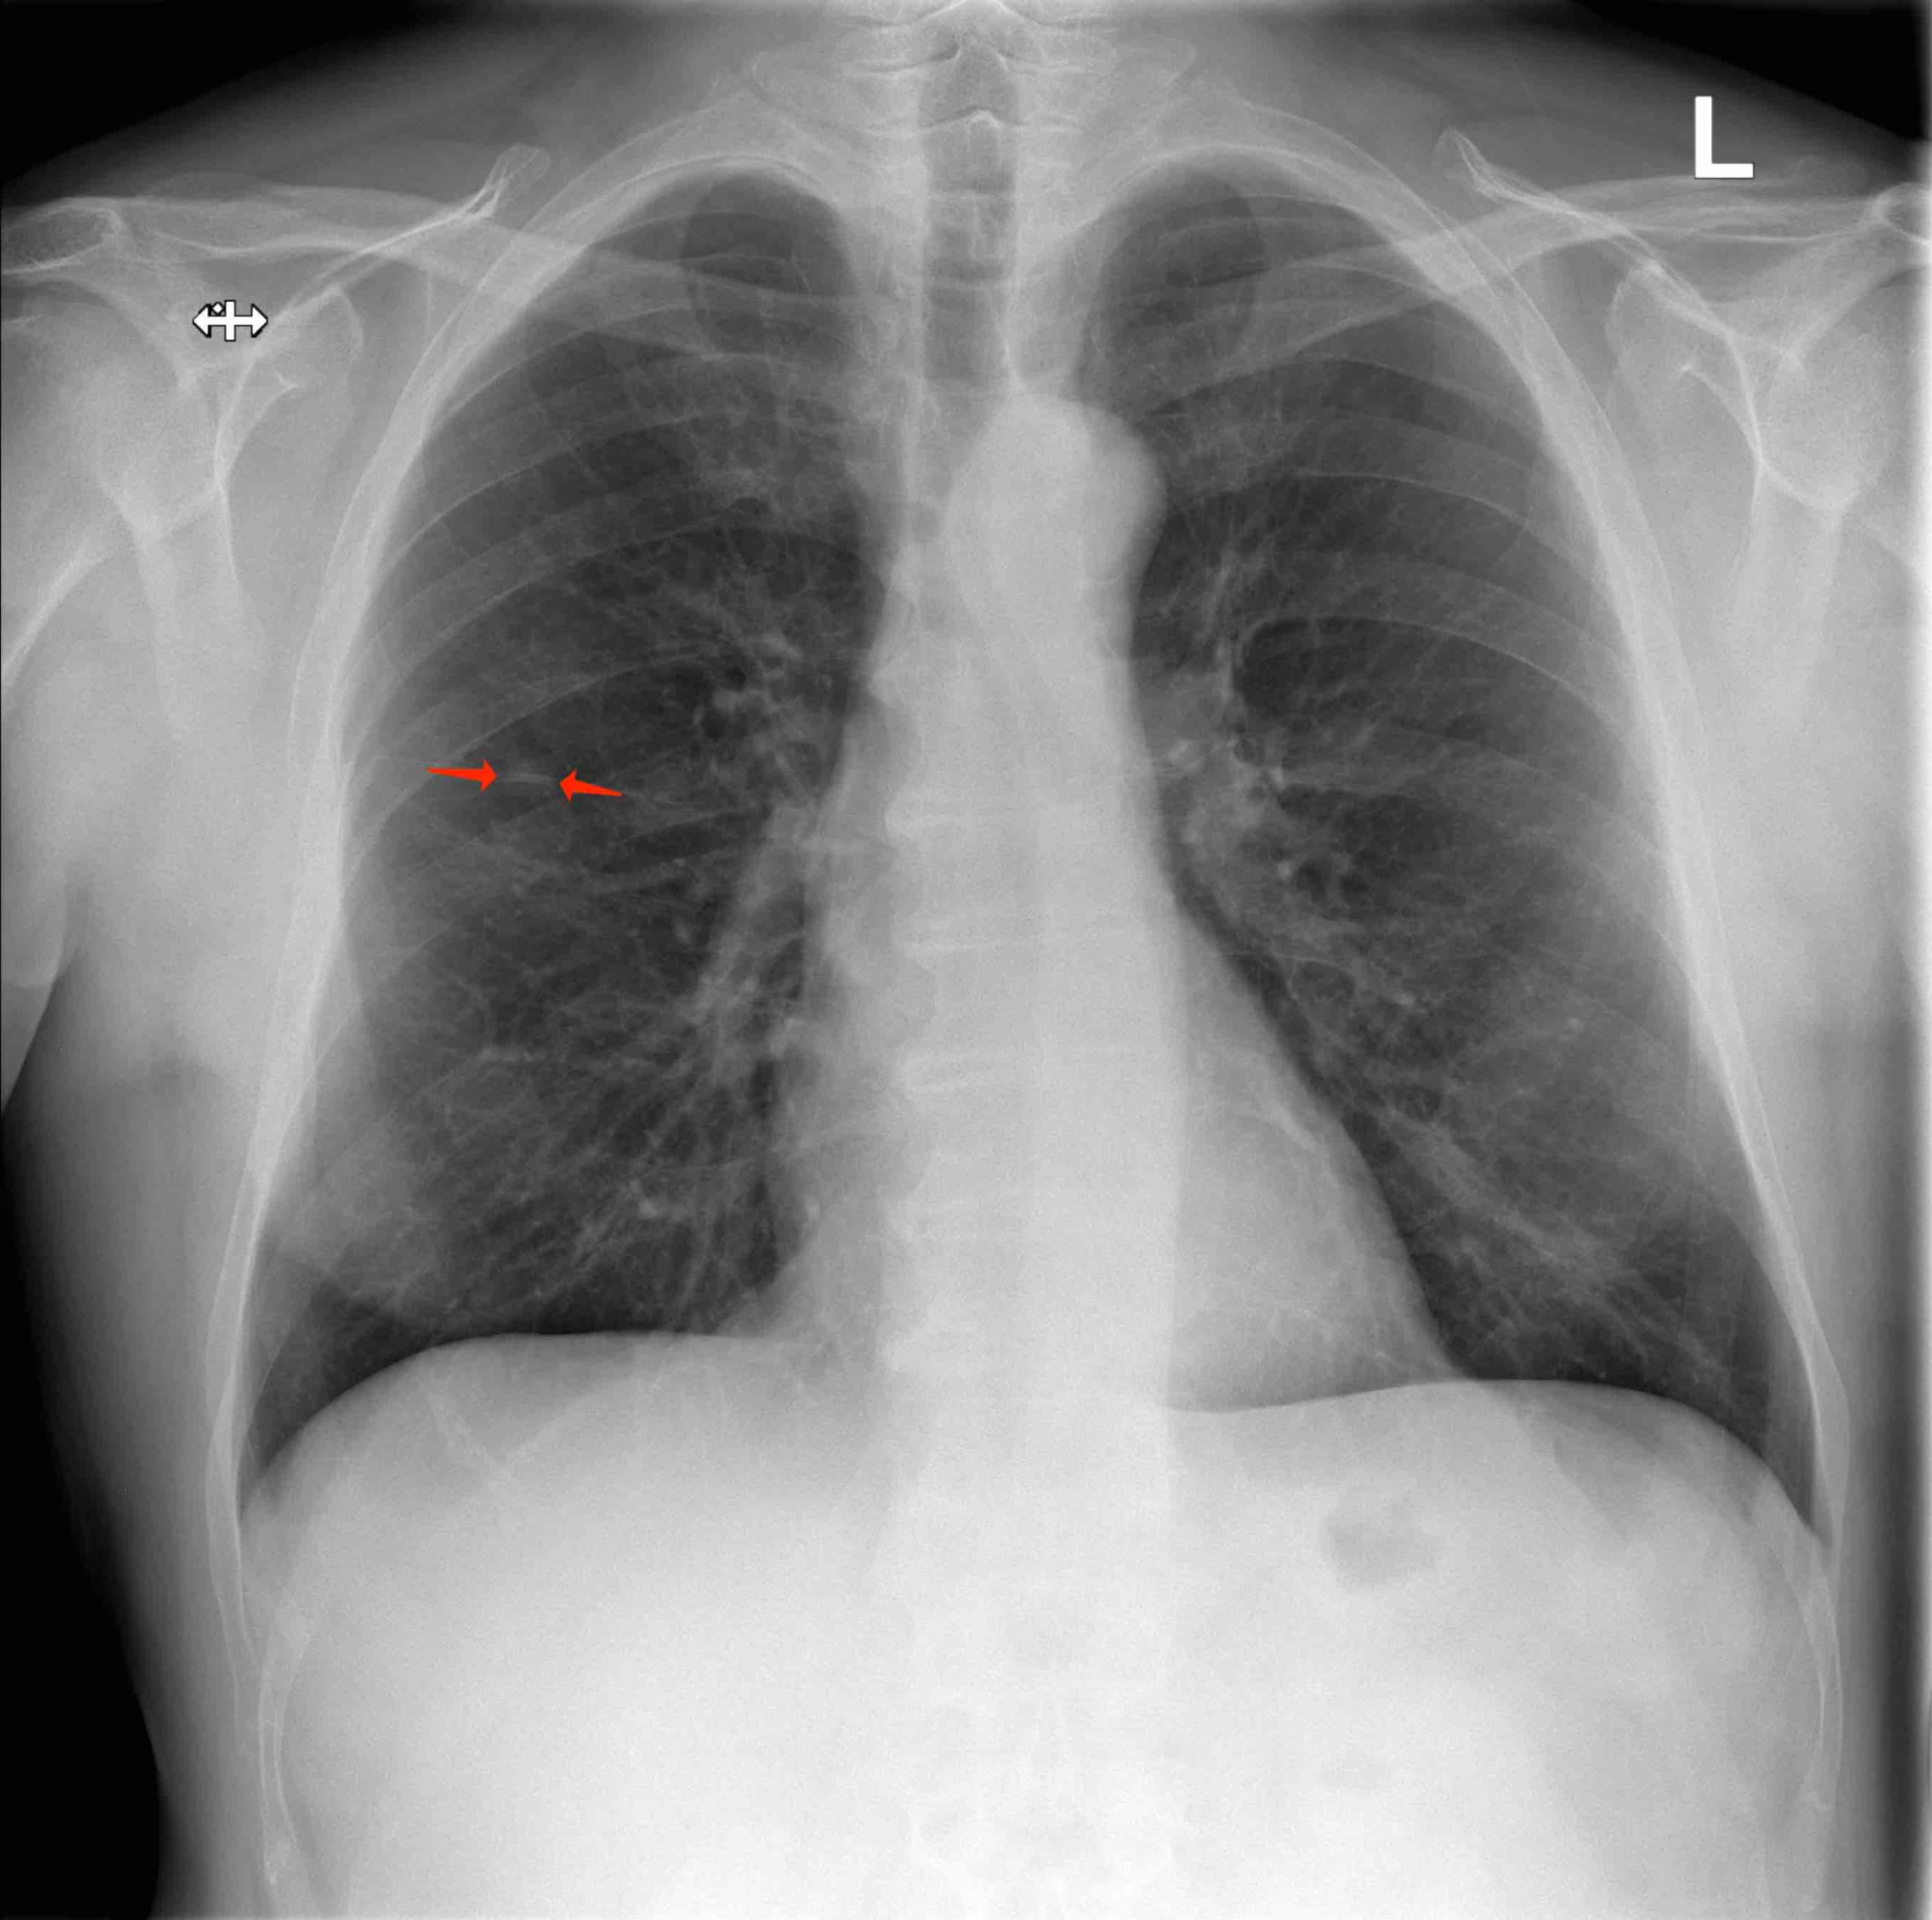

CXR – lesion in the right upper lobe.

A 64-year old male was referred due to an asymptomatic lesion in the right upper lobe. He reported symptoms of respiratory infection several weeks ago with cough, purulent sputum and mild fever up to 38°C. Chest X-ray (CXR) was performed since he was an ex-smoker with 70 pack-years of smoking history. The lesion persisted three weeks later on the follow-up CXR. The patient denied chronic illnesses. He regularly took aspirin 100 mg/d. After the short course of treatment with amoxicillin-clavulanic acid his symptoms had gradually disappeared, and he had no further complaints. Clinical examination including detailed examination of  respiratory system was in normal range. Blood biochemistry, coagulation tests and differential blood count were in the normal range, except CRP was slightly elevated to 12,6 mg/l.

Lung function tests: vital capacity 4930 ml (110%), FEV1 2720 ml (79%), TI 55%, diffusion capacity 81%. There was no response in FEV1 to bronchodilator challenge test. On the CT scan a solitary 12 mm spiculate lesion was discovered in the 3rd segment of the right upper lobe near the interlobar fissure, suspicious for primary long tumor. No metastases or enlarged lymph nodes were observed. Additionally, moderate centrilobular emphysema was described.

CT-scan – lesion in the 3rd segment of the right upper lobe (axial, coronal and sagittal reconstruction)